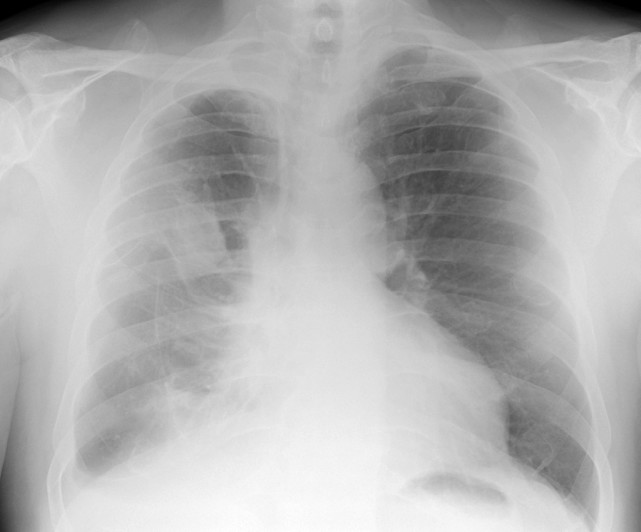

肺部作为人体重要的器官之一 , 无时无刻都在掌握着人体与外界的外流 。 伴随着人类社会压力的提升 , 肺部疾病的比例也在患者比例中开始上升 , 越来越多的人也开始意识到除了胃跟肝 , 肺部也是一个需要保养的器官 。

作为身体内负责呼吸的器官 , 一旦出现问题身体就会有对应的现状表现出来 。 医学临床数据表明 , 大多数患有肺病的患者大多数都身形消瘦 , 并且皮肤干燥 , 肤色与正常人相比相对晦暗 。

除此以外在消化系统上会有排便不正常的现象 , 这些都是因为肺部疾病引起的其他器官的不适反应 。 在外在表现上 , 有的患者会体毛生长旺盛 , 并且手指或足趾有增生出现 。

这些都是肺病患者的几种常见表现 , 如果身体有以上几种现象出现建议及时去医院问诊 , 因为以上几种现象是患有肺部疾病的常见表现 。